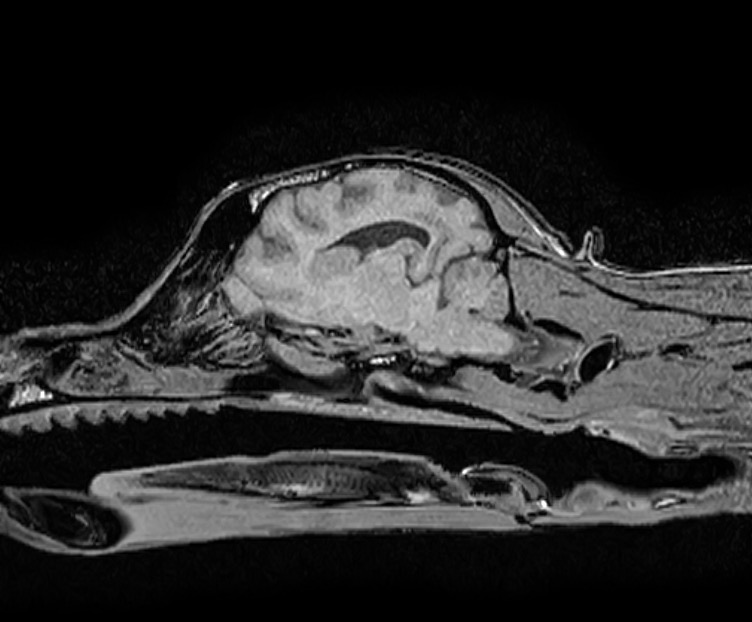

肉芽腫性髄膜脳脊髄炎と診断した犬の1例(MRI、GME、脳炎、神経症状、ふらつく、眼振)

治療開始2週間後に実施した頭部MRI再検査では、脳の浮腫といった脳圧亢進所見、大脳後頭葉領域の炎症所見がすべて改善し、 わんちゃん自身もふらつきや眼振は無くなり、元気や食欲といった一般状態も極めて良好でした。

脳炎は治療をストップすると再発する恐れがあるため現在も治療継続中ではありますが、

早期診断→早期治療を行えたため、現在も良好な経過をたどっています。